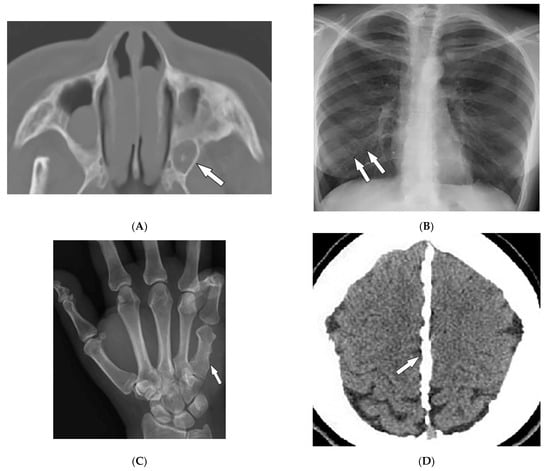

2.5. Granulomatosis with Polyangiitis

| Granulomatosis with polyangiitis (Wegner’s) | Palpable purpura Subcutaneous nodules Pyoderma-gangrenosum-like ulcerations Lung lesions and hemoptysis Glomerulonephritis Peripheral neuropathy, mononeuritis multiplex Chronic sinusitis and saddle nose deformity | Bilateral cavitary lung lesions with a ground-glass halo sign Mucosal thickening Nasal septal perforation Hyperostosis |